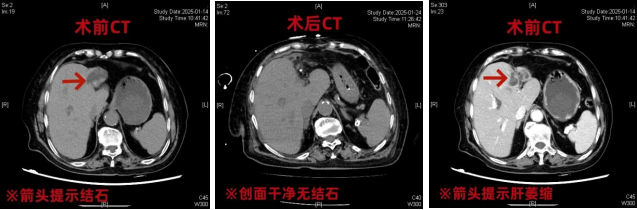

90岁的徐奶奶因复杂左肝胆管结石辗转求医,多家医院因高龄风险建议保守治疗。经过充分的术前评估沟通,徐奶奶全家希望能接受机器人手术。

最终,我院肝胆胰医学中心田毅峰教授团队决定迎难而上,成功完成达芬奇机器人辅助左半肝切除、胆道探查微创手术。一次正确的选择为徐奶奶带来了新的希望,这也是我省首例超高龄患者成功完成的机器人复杂胆道手术。